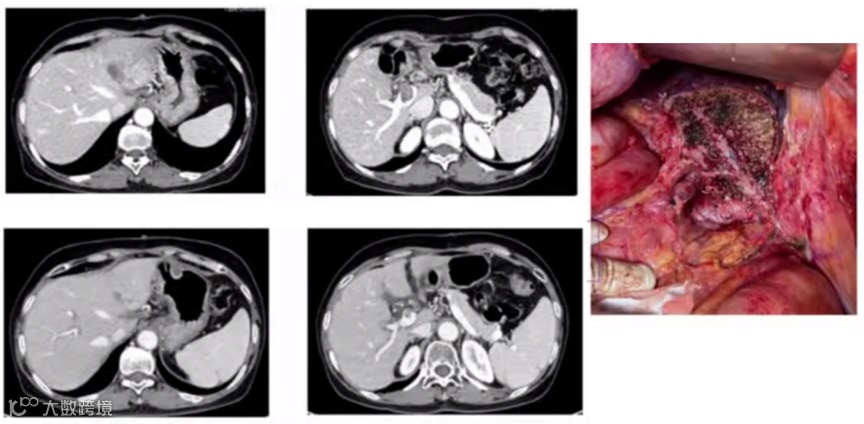

2. 肝静脉系统栓堵术(LVD)可以增加剩余肝体积达到转化切除

1位术前诊断为中央型肝癌(Ⅴ、Ⅷ段交界处)的53岁男性患者,因剩余肝脏体积(FLR)不足,无法行标准右半肝切除术,而行LVD术诱导FLR增生。LVD术后1、2及3周评估患者一般情况并复查腹部CT,评估FLR体积和剩余肝脏/体质量比。结果显示,患者LVD术前FLR为24.2%,剩余肝脏/体质量比为0.459%;LVD术后第1、2及3周复查FLR,分别为29.5%、38.3%和44.4%,剩余肝脏/体质量比分别为0.545%、0.707%和0.820%。患者于LVD术后第25天顺利施行了标准右半肝切除术,术后安全康复出院。

由此可见,LVD可使剩余肝脏体积快速增大,可让预计FLR不足的肝癌患者有接受第二阶段根治性手术治疗的机会,是一项有效诱导FLR增生的新技术。